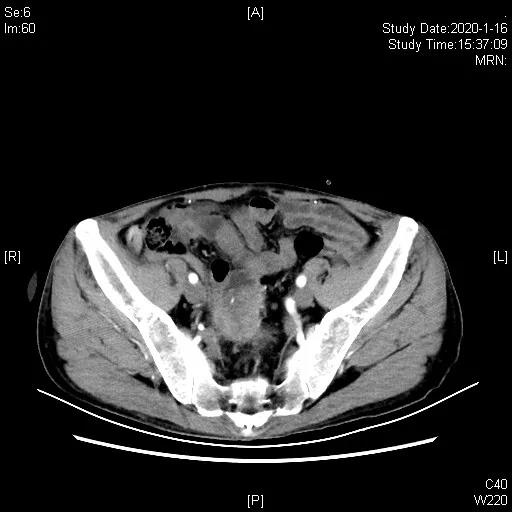

二线治疗:2019-12-04、12-29单药“白蛋白结合紫杉醇0.2d1,5”化疗2程,II度白细胞减少。2020-01-16胸腹部CT示病灶较前缩小,近期疗效评估稳定(SD)。01-18、02-26“白蛋白结合紫杉醇0.2d1,0.1d5”再次化疗2程,胸腹部CT示腹腔病灶增大,期间反复尿路感染,予以抗感染治疗。

二线化疗2周期后,缩小,评估SD